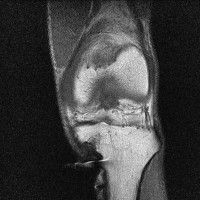

무릎 mri 간단히 봐주실 수 있으시나요 ㅠㅠ

안녕하세요 8년전 십자인대 수술하고 최근 무리한 운동에 무릎 불편감이 생겨서

mri 찍었습니다.

진단결과는 첫 찍은 병원에서 활액막염 이라는 진단을 받았습니다. 혹시 봐주실 수 있으실까요?

올라온 MRI가 단편적이라서 정확한 진단에 어려움이 있지만 십자인대에는 큰 이상이 있지는 않은것 같으며, 무릎관절내 물이 있는 것으로 보아 활액막염의 진단이 맞을 것 같습니다.

하지만 단편적인 영상이기 때문에 촬영병원에서 정확한 판독지 등을 받으시는 것이 좋겠습니다.